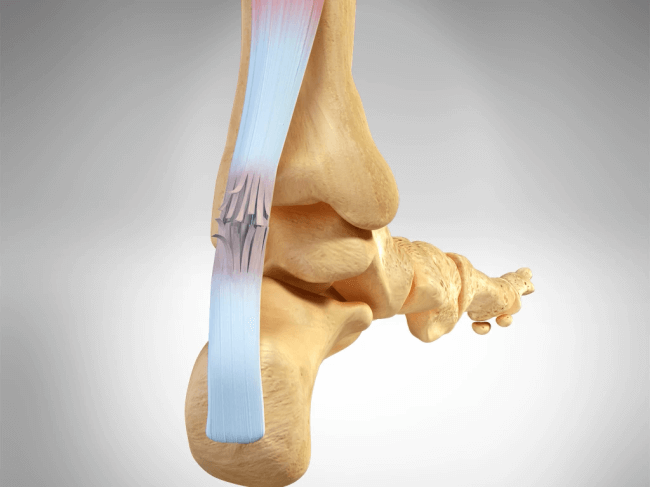

Patologie dei Tendini della Caviglia e del Retropiede

Comprendono: tendiniti, tenosinoviti, infiammazione delle inserzioni dei tendini o delle fasce, sublussazioni o rotture parziali o complete dei tendini. Il disturbo più frequente è il dolore progressivo che si accentua con il movimento. A volte una sollecitazione anormale del tendine interessato è causata da una deformità del piede o da una modificazione volontaria della meccanica della fase di appoggio, conseguenza del tentativo del paziente, di evitare il carico su una lesione dolente della fascia plantare, inaftti si ottengono benefici con l’uso di antinfiammatori.